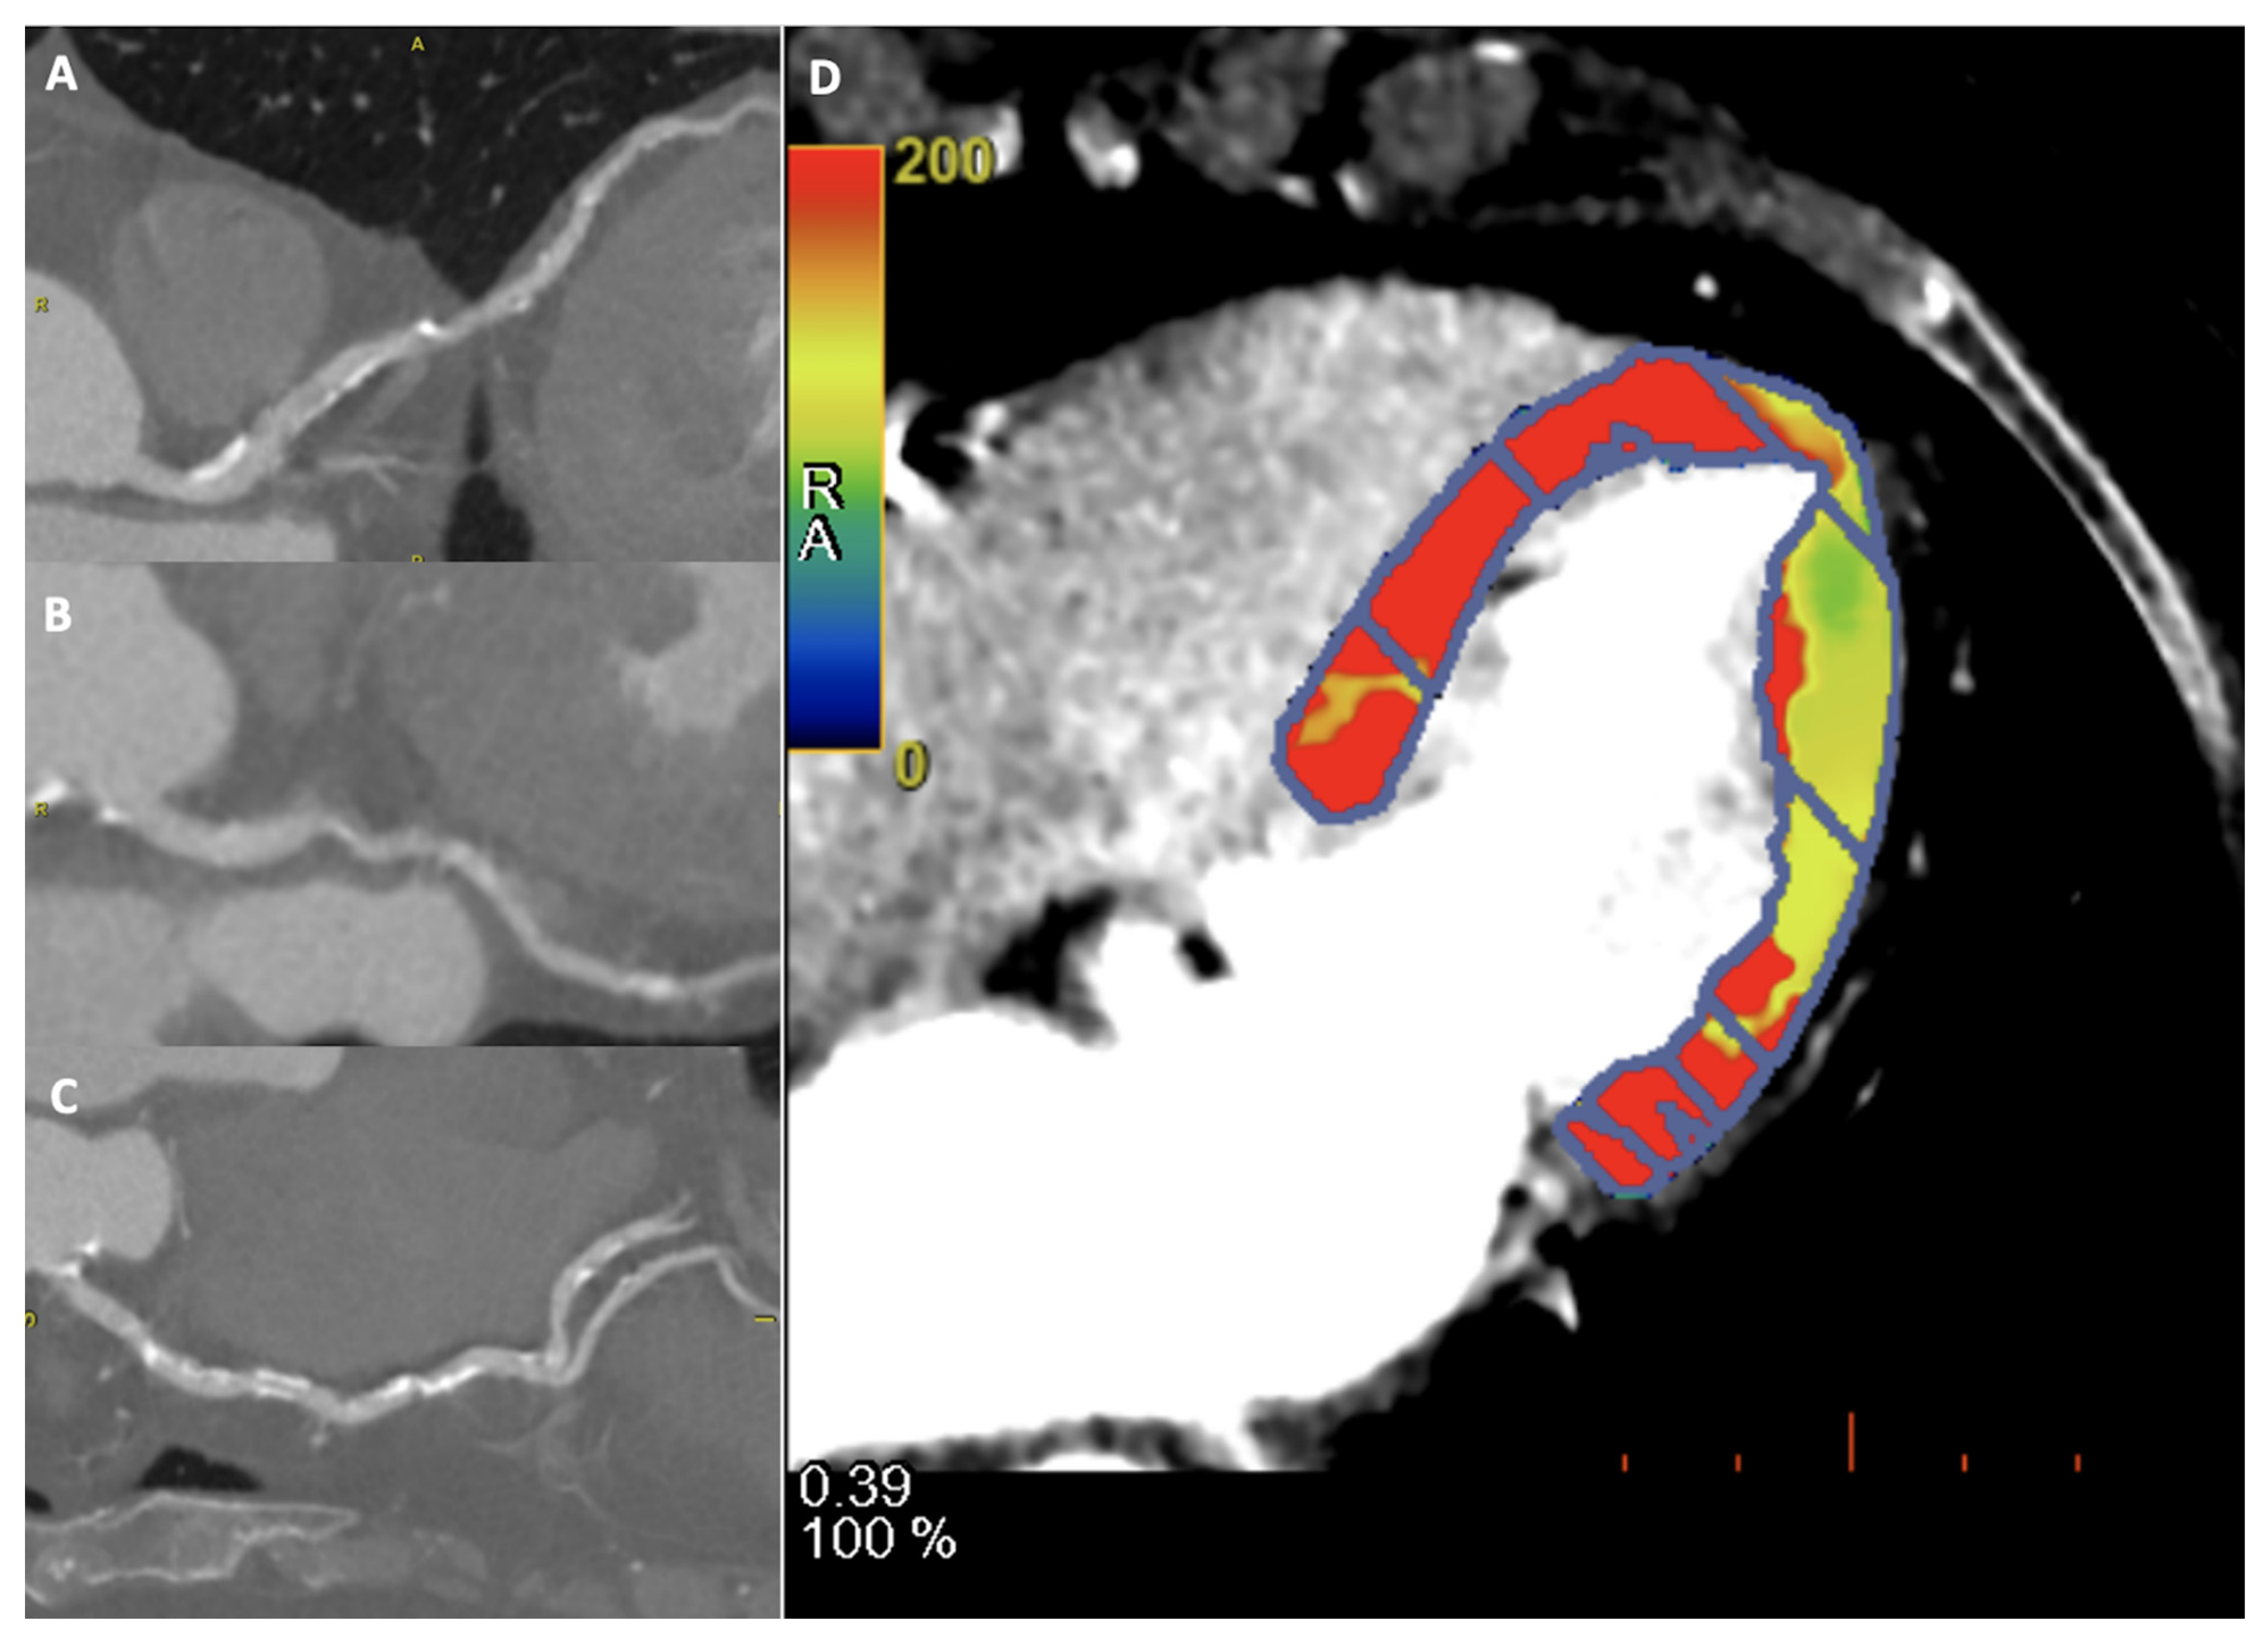

A representative case of FFRct and myocardial perfusion are shown in Figure 2 and Figure 3, respectively.

Figure 3.

A 60-year-old female patient underwent to CCTA and dynamic CT perfusion for suspected coronary artery disease. Diffuse coronary calcification on left anterior descending artery (A), left circumflex (B) and right coronary (C), showing mild reduction of flow in dynamic CT perfusion on lateral wall, in particular at the apical segment (D).